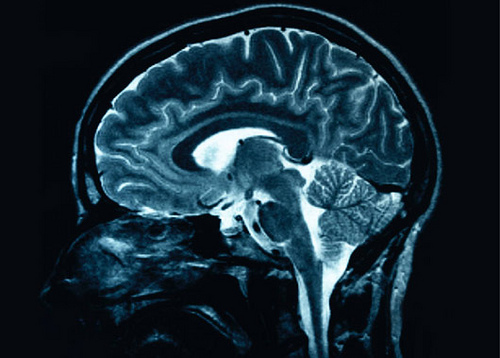

Did you know that if you’ve suffered a head injury earlier in life, you may be more likely to develop Alzheimer’s or another form of dementia in your senior living years?

While there is no single known cause of Alzheimer’s, medical research has shown that there is a direct link between dementia and Traumatic Brain Injuries (TBI).

- Clinical research indicates that the link between TBI and Alzheimer’s are related to brain chemistry. Current studies are focusing on how the upset of brain chemistry from a traumatic brain injury could relate to the hallmark protein abnormalities (beta-amyloid and tau) that have been linked to Alzheimer's.